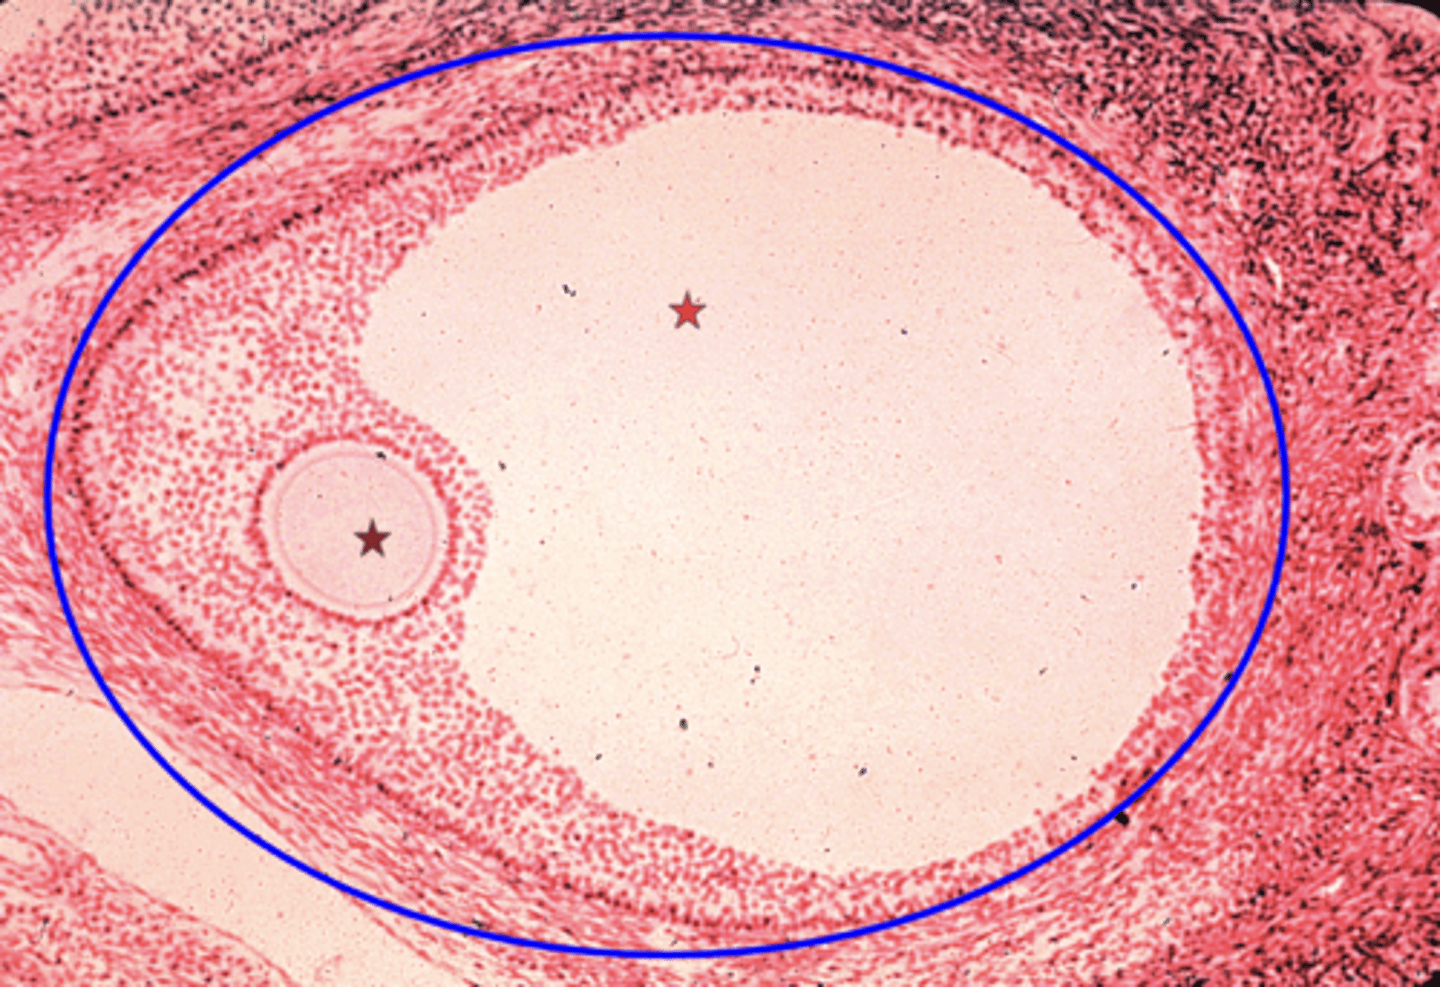

Graafian follicle

What is the blue circle?

Primary oocyte

What is the brown star?

Antrum

What is the red star?